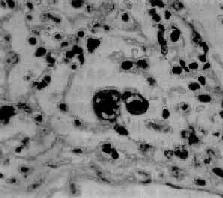

腺病毒肺炎

图9-21 腺病毒肺炎

图中央可见肿大肺泡上皮细胞中的核内包含体